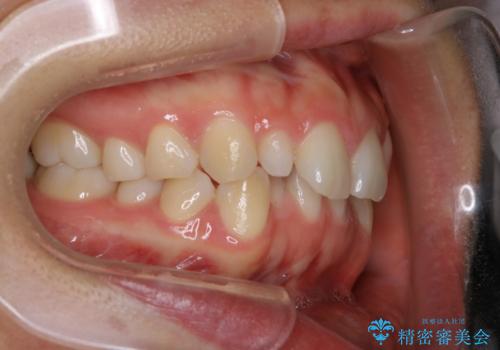

- 上の前歯が大きい事と下の前歯のがたつきを気にされてご相談にいらした方です。上の2番目の歯が矮小歯であったため、矯正治療にて歯のスペースを作った後、矮小歯には被せ物をして前歯のバランスを整えました。

歯科技工士さんとの打ち合わせを重ね、周囲の歯としっかりなじむ天然歯のような被せ物をお作りすることが出来ました。

矯正治療と補綴治療をうまく組み合わせることで、美しい口元に仕上げることが出来ました。矯正治療、補綴治療をまとめて行える総合歯科治療を体現した治療といえます。